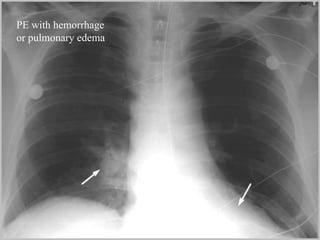

Diagnosis CXR Usually reveals a non specific abnormality.  14% normal Classic abnormalities include: Westermark’s Sign - focal oligemia Hampton’s Hump - wedge shaped density Enlarged Right Descending Pulmonary Artery (Palla’s sign)

PE with hemorrhage or pulmonary edema

PE with hemorrhageor pulmonary edema